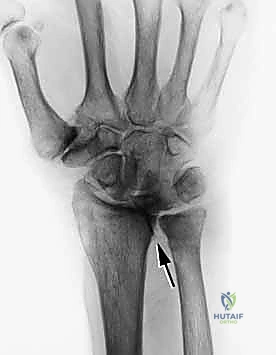

يؤدي الروماتويد إلى تآكل العظام وخلع المفاصل، خاصة في مفصل المعصم (المفصل الزندي الكعبري السفلي). هذا الخلع يؤدي إلى بروز نتوءات عظمية حادة (Bone Spurs). عندما ينزلق الوتر فوق هذا النتوء العظمي الحاد آلاف المرات يومياً، فإنه ينقطع كما ينقطع الحبل عند احتكاكه بحافة صخرة حادة (يُعرف هذا بمتلازمة فوغان-جاكسون Vaughan-Jackson Syndrome).